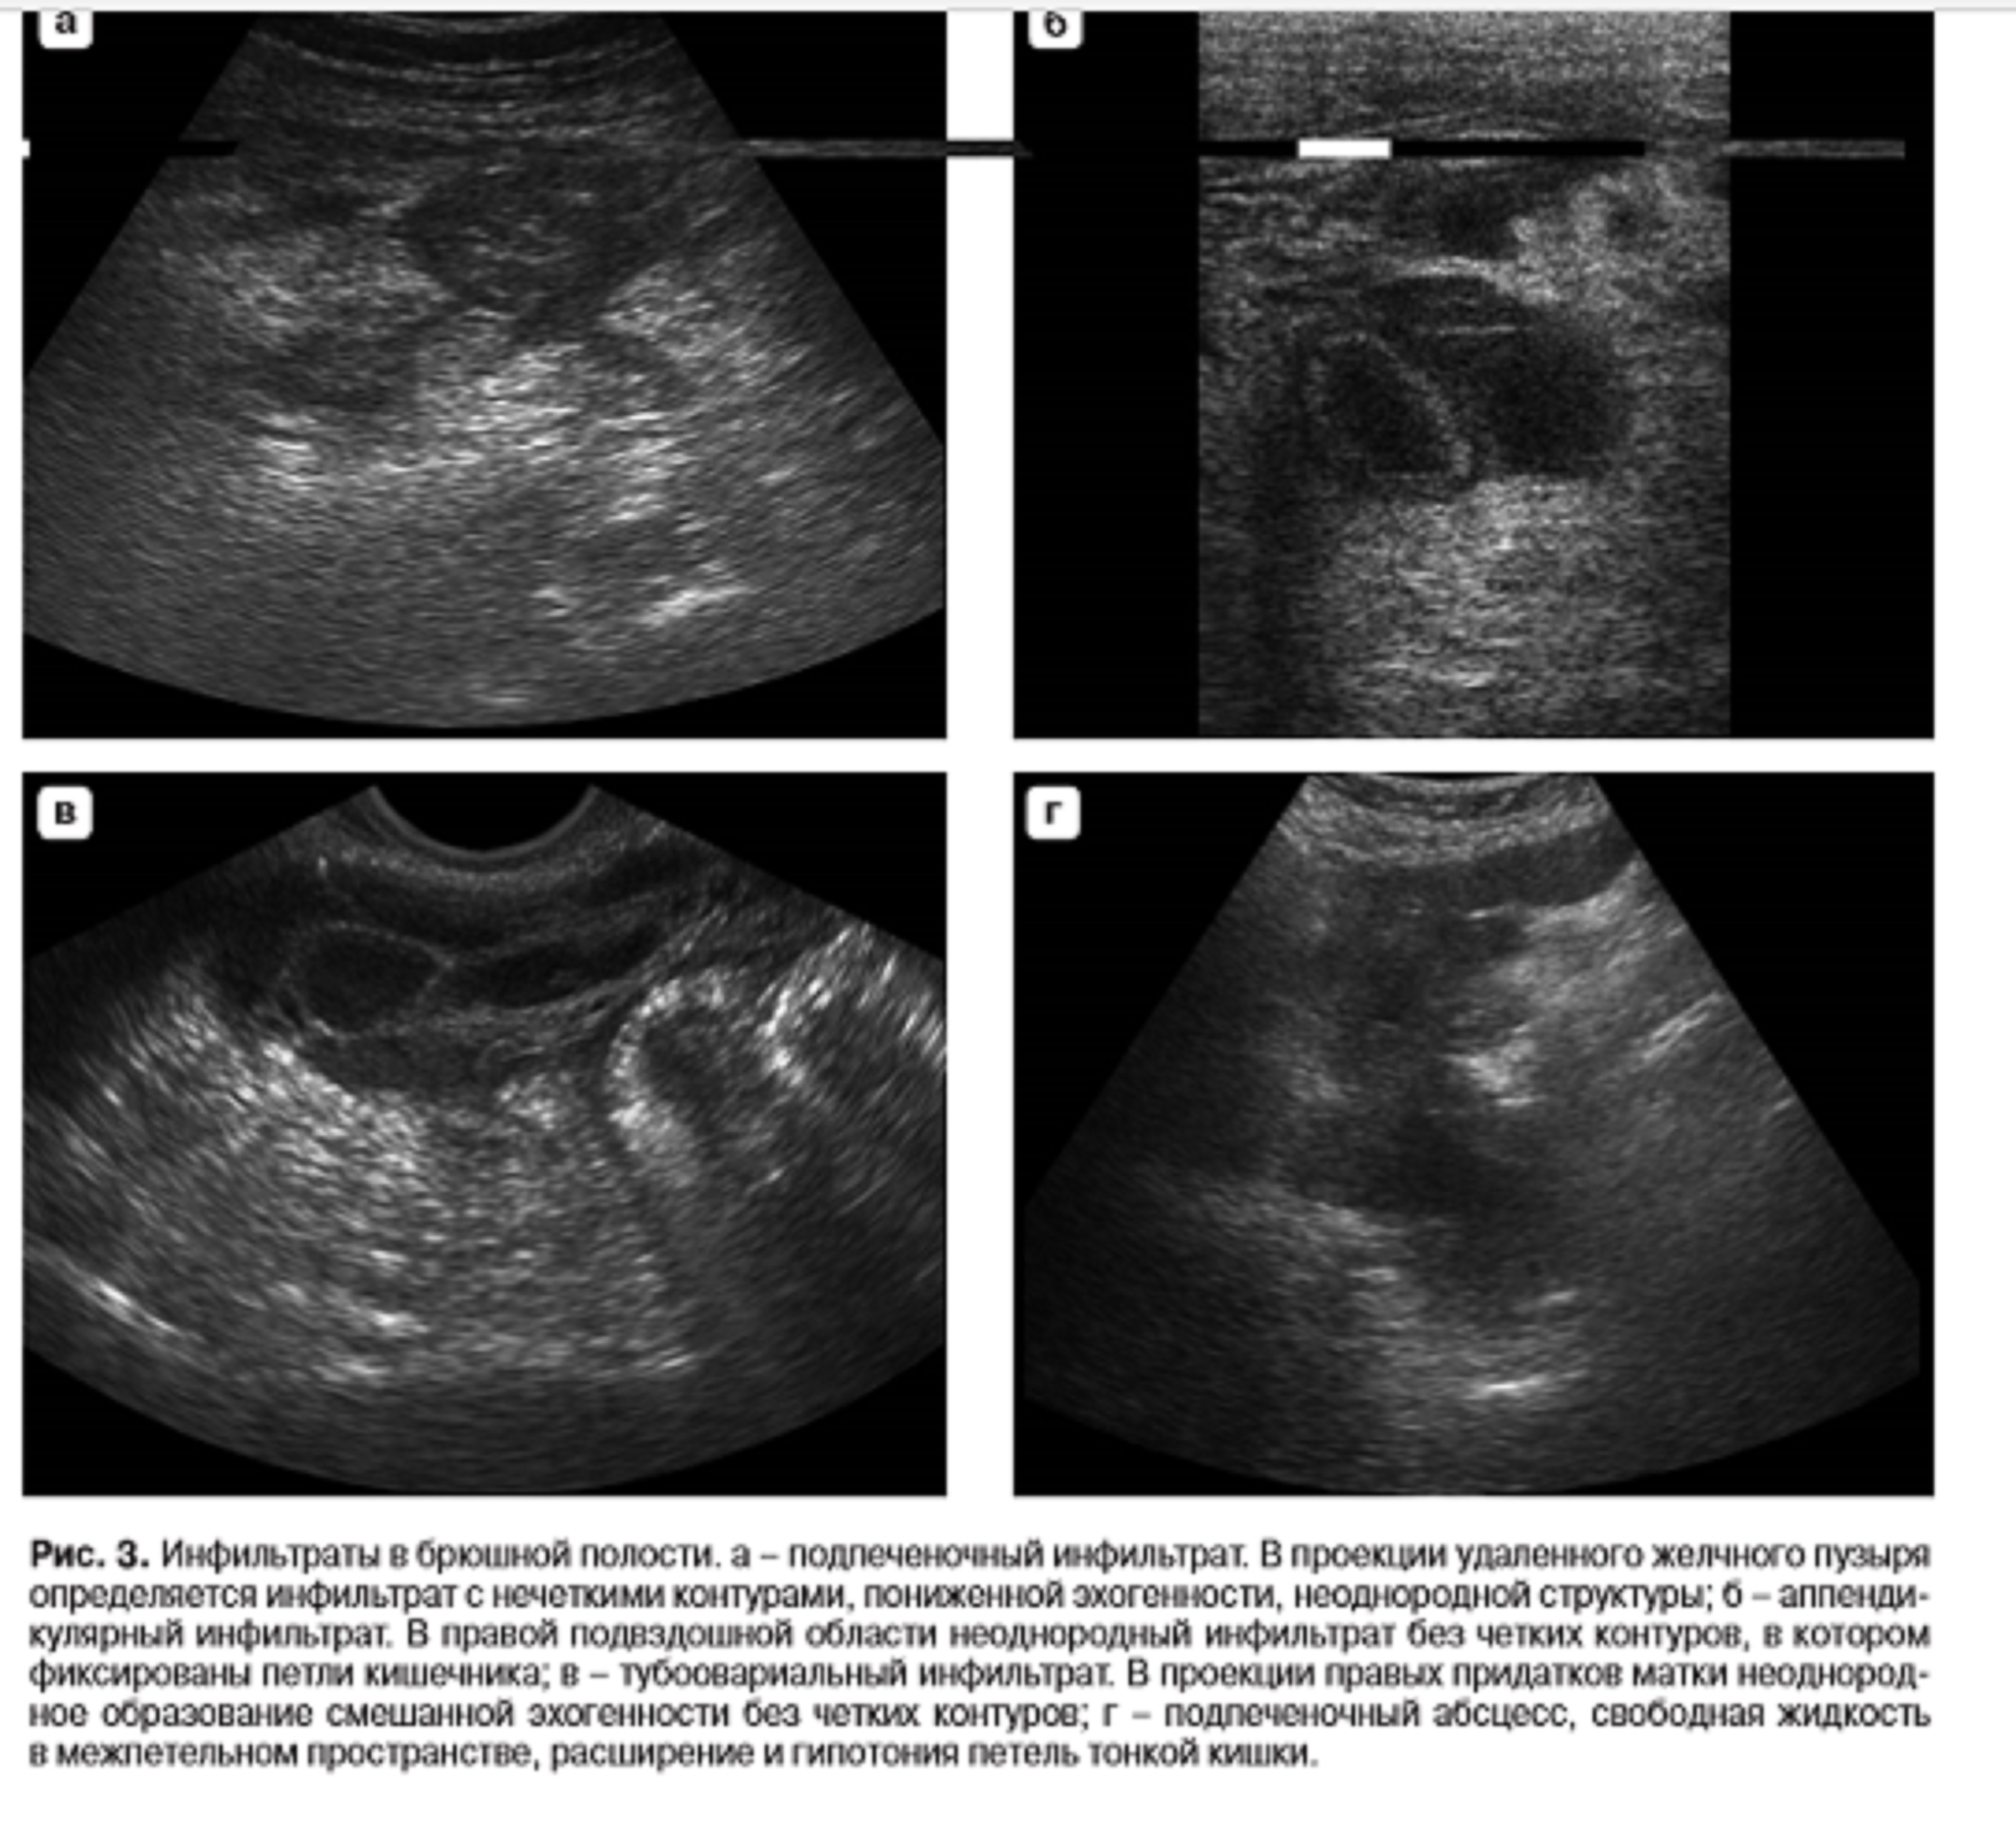

так траткуют инфильтраты - неоднородное образование, нечеткие контуры(инфильтарация! в окружающие ткани!)

Есть большой сальник, прикрывающий толстую кишку и с небольшим отграниченным скоплением жидкости, что всё вместе и называется "инфильтрат с абсцедированием".

Такая же картина может наблюдаться при остром холецистите, аппендиците, когда сальник отграничивает зону патологического процесса. Есть еще другие инфильтраты - парапанереатические, околокишечные (например, при дивертикулитах), параовариальные и т.д. Не говорю уже про опухолевые.

Все они выглядят практически одинаково. Они неоднородны в смысле того, что включают органы-мишени и часто окружающие органы, но они однородны в смысле отсутствия жидкостного компонента - в этом случае предполагается его абсцедирование.